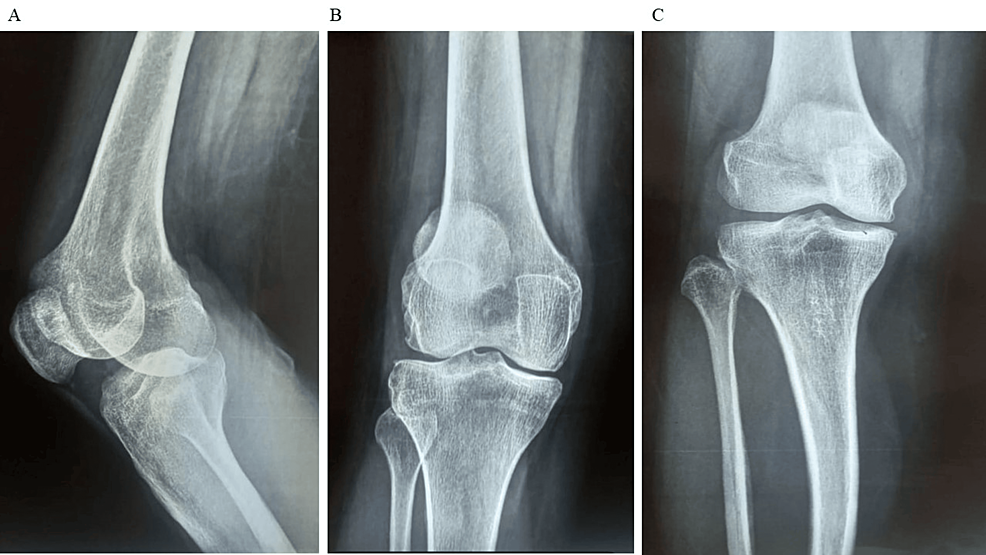

平均WOMAC評分從基線(xiàn)時(shí)的56.8±11.5下降到六個(gè)月時(shí)的41.2±10.6。此外,還監測了不良事件的發(fā)生情況,報告了七起不良事件,占參與者的28.0%。這些發(fā)現強調了該治療在六個(gè)月內減輕疼痛和改善功能結果方面的有效性。下圖2顯示了開(kāi)始干細胞治療后骨骼的側視圖和前后視圖。?

圖2:顯示了開(kāi)始干細胞治療后骨骼的側視圖和前后視圖

圖2:A:干細胞治療后(側視圖),B:干細胞治療后前后位 (AP) 視圖,C:干細胞治療后前后位 (AP) 視圖。